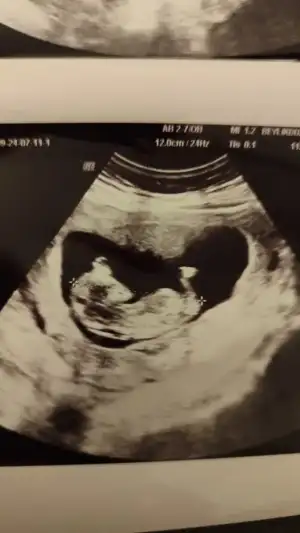

Biz bugün 12+0 dık. Doktor herşeyin yolunda göründüğünü söyledi. Gelişimi güzel görünüyor dedi. Folik asiti bıraktırdı 3 tane ilaç yazdı biri demir diğer ikisi ne bilmiyorum henüz almadım. Cinsiyet tahminlerinizi alırız ❣️

Eklentiler

• IMG_20240711_222412.webp

IMG_20240711_222412.webp

18,1 KB · Görüntüleme: 92